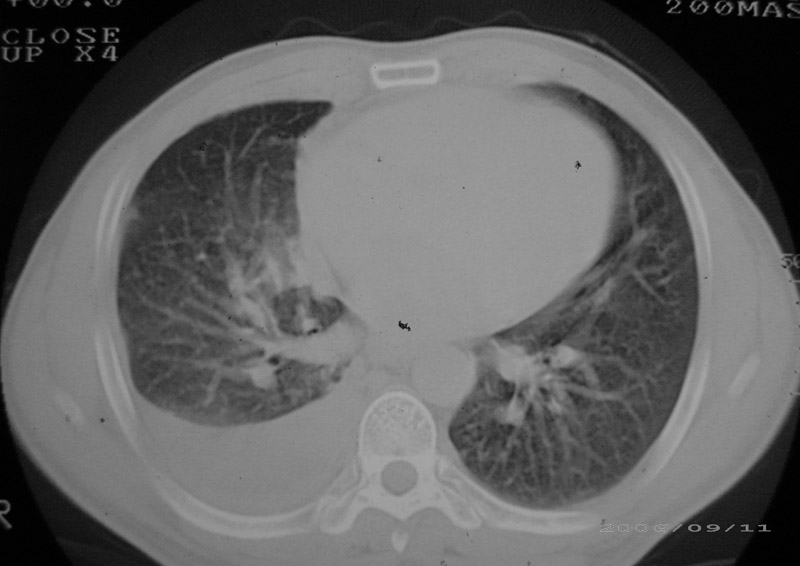

以下是引用守望可可西里在2006-9-11 15:29:00的发言:[br][br] ct平扫表现:右侧胸膜腔缩小,积液,胸膜增厚且不均匀、不规则,以纵隔胸膜增厚为主,边缘呈锯齿状,并见附壁内突之结节状肿块影。右肺含气量减少,纹理聚集,右肺门中下部见数个肿大的淋巴结。纵隔无移位,内未见明显肿大淋巴结,双侧主支气管以及各叶、段支气管比较通畅。。[br] 考虑:右侧胸膜恶性间皮瘤,伴肺门淋巴结转移。